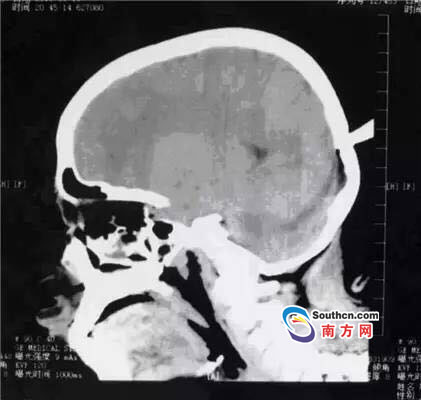

接到小玲受傷的消息,東莞市第三人民醫(yī)院急診科立即啟動了急癥危重患者搶救流程。急癥頭部CT顯示,飛鏢已穿透小玲的顱骨,并突破硬腦膜,情況非常兇險(xiǎn),小玲命懸一線。

此時,小玲也處于極度恐懼和不安中。醫(yī)生表示,必須及時手術(shù)取出異物、止血并妥善處理顱內(nèi)相關(guān)損傷,否則飛鏢將進(jìn)一步損傷腦組織,引起二次傷害,甚至可能引發(fā)顱內(nèi)大出血。搶救刻不容緩,醫(yī)院神經(jīng)外科醫(yī)師立即與麻醉手術(shù)科聯(lián)系,開通綠色通道準(zhǔn)備急診手術(shù)。

開顱還是不開顱?這是擺在神經(jīng)外科醫(yī)生面前最重要的問題。此時的檢查結(jié)果無法判斷有無血管和腦組織的損傷,開顱手術(shù)可以直接看到損傷的情況,及時進(jìn)行處理,但是如果飛鏢沒有損傷大血管,開顱的話就會造成比較大的創(chuàng)傷;不開顱手術(shù),手術(shù)的全過程造成的損傷就會減少,但是如果有大血管的損傷,不開顱直接拔出飛鏢,就不能及時進(jìn)行止血和清創(chuàng)。

兩種選擇都是機(jī)會與風(fēng)險(xiǎn)并存的,最后神經(jīng)外科通過會診,在充分征求家屬意見的基礎(chǔ)上,決定進(jìn)行不開顱手術(shù),同時,也充分考慮手術(shù)風(fēng)險(xiǎn),做好開顱手術(shù)的一切準(zhǔn)備。